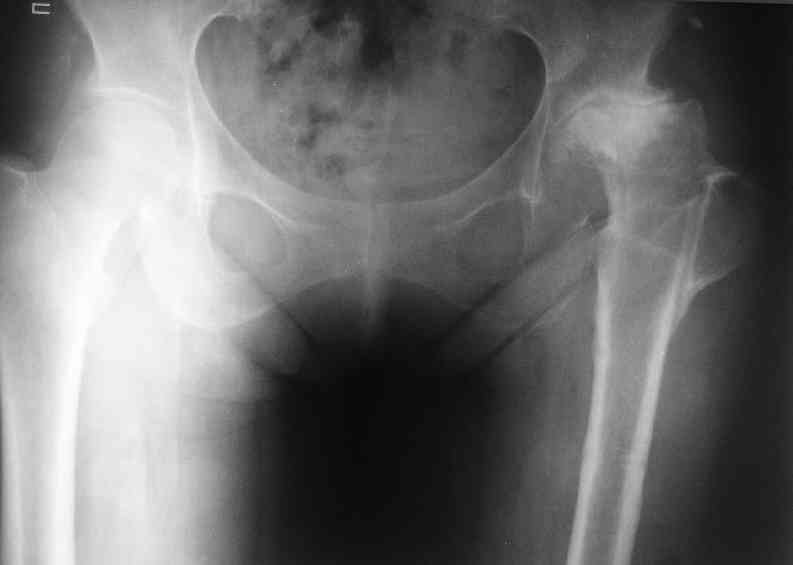

AV> опираясь на стул. На ногу не наступает. Укорочение 8 см. Иногда

А за счет чего такое укорочение? По снимку не видно соответствующего дефекта. Ну плюс приводящая контрактура - но все равно как-то уж больно много. Может, сделать снимки и таза обзорный с обоими проксимальными отделами бедра, и коенный суставов с приложенной линейкой какой?

Судя по снимку, максимум истинное укорочение около 4 см, что может быть коррегировано интраоперационно. Вопрос в другом: куда ставить ацетабулярный компонент в истинную или во вновь сформированную ( впадина диспластичная).

По рентгенограммам укорочение не более 4 см, остальное возможно за счет контрактуры. Опыта с низведением аппаратом Илизарова нет, но мы одномоментно такие укорочения корригировали вполне успешно (в год 5-10 именно таких и проходит). Лишние этапы пожалуй только будут способствовать инфекции. Доступ чаше применяем передне-наружный, а вот протез наверное поставили бы здесь на цементе - остеопороз выражен.

Ортопедическое укорочение пострадавшей ноги может быть и 7, и 10 см. за счет контрактур в тазобедренном суставе, а вот истинное укорочение, судя по представленным рентгенограммам, вряд ли больше 4 см.